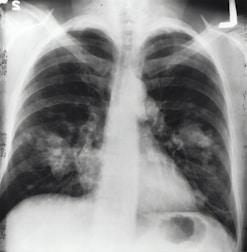

Cuidados especializados para a saúde respiratória infantil.

Realizamos testes respiratórios para monitorar a saúde pulmonar.